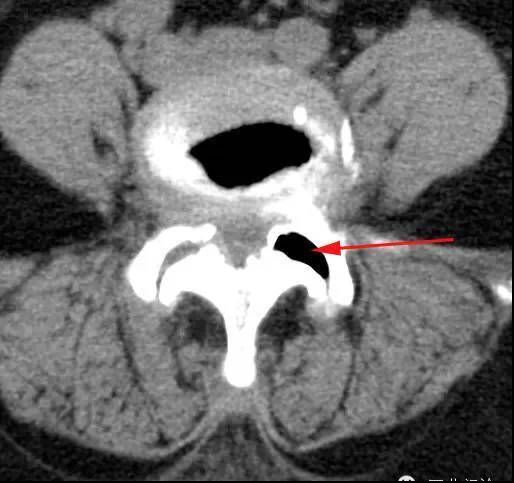

腰部损伤,伤后立即发生异乎寻常的剧烈腰痛。患者往往屈身侧卧,腰不能挺直,不敢动弹,唯恐别人触碰,常被误诊为急性腰肌扭伤。其实,确切的诊断应是腰椎关节滑膜嵌顿,或叫腰椎小关节紊乱症,俗称小关节紊乱。此外,腰椎小关节慢性退变,关节软骨磨损、骨质增生、关节囊纤维化、关节腔狭窄、关节突内聚等病因造成小关节慢性损伤,刺激脊神经内侧支所致疼痛,为慢性腰椎小关节综合征。慢性腰椎小关节综合征患者远远多于急性损伤患者。下图中可见模型中已经CT中小关节的位置。大比例。那么腰腿痛最常见的病因是什么?

小关节损伤模型示意图(左图)小关节损伤CT(右图)